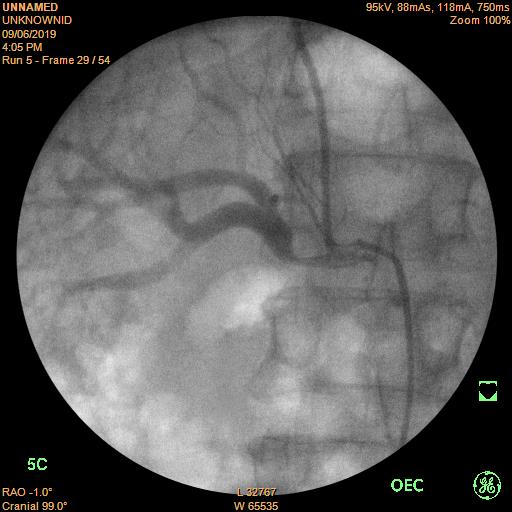

Bệnh nhân vào bệnh viện Trường Đại học Y dược Huế do chấn thương thành ngực, đụng dập phổi, được điều trị tích cực tại khoa ngoại Chấn thương chỉnh hình, được hội chẩn điều trị hạ huyết áp từ khoa nội Tim mạch nhưng vẫn chưa kiểm soát được huyết áp cho dù tình trạng cấp tính do chấn thương đã dần ổn định. Nhận định đây là một trường hợp bệnh lý tăng huyết áp khó, có nhiều bệnh kèm phức tạp, khoa nội Tim mạch đã nhận bệnh điều trị và làm thêm các xét nghiệm chuyên sâu để tìm nguyên nhân gây tăng huyết áp khó kiểm soát ở bệnh nhân này. Sau khi chụp cắt lớp vi tính (CTscan) bụng có thuốc cản quang và chụp mạch máu thận (chụp DSA), bệnh nhân được xác định hẹp 95% đoạn gần gốc động mạch thận phải, động mạch thận trái bình thường.

Hình 1. Hẹp 95% động mạch thận phải.